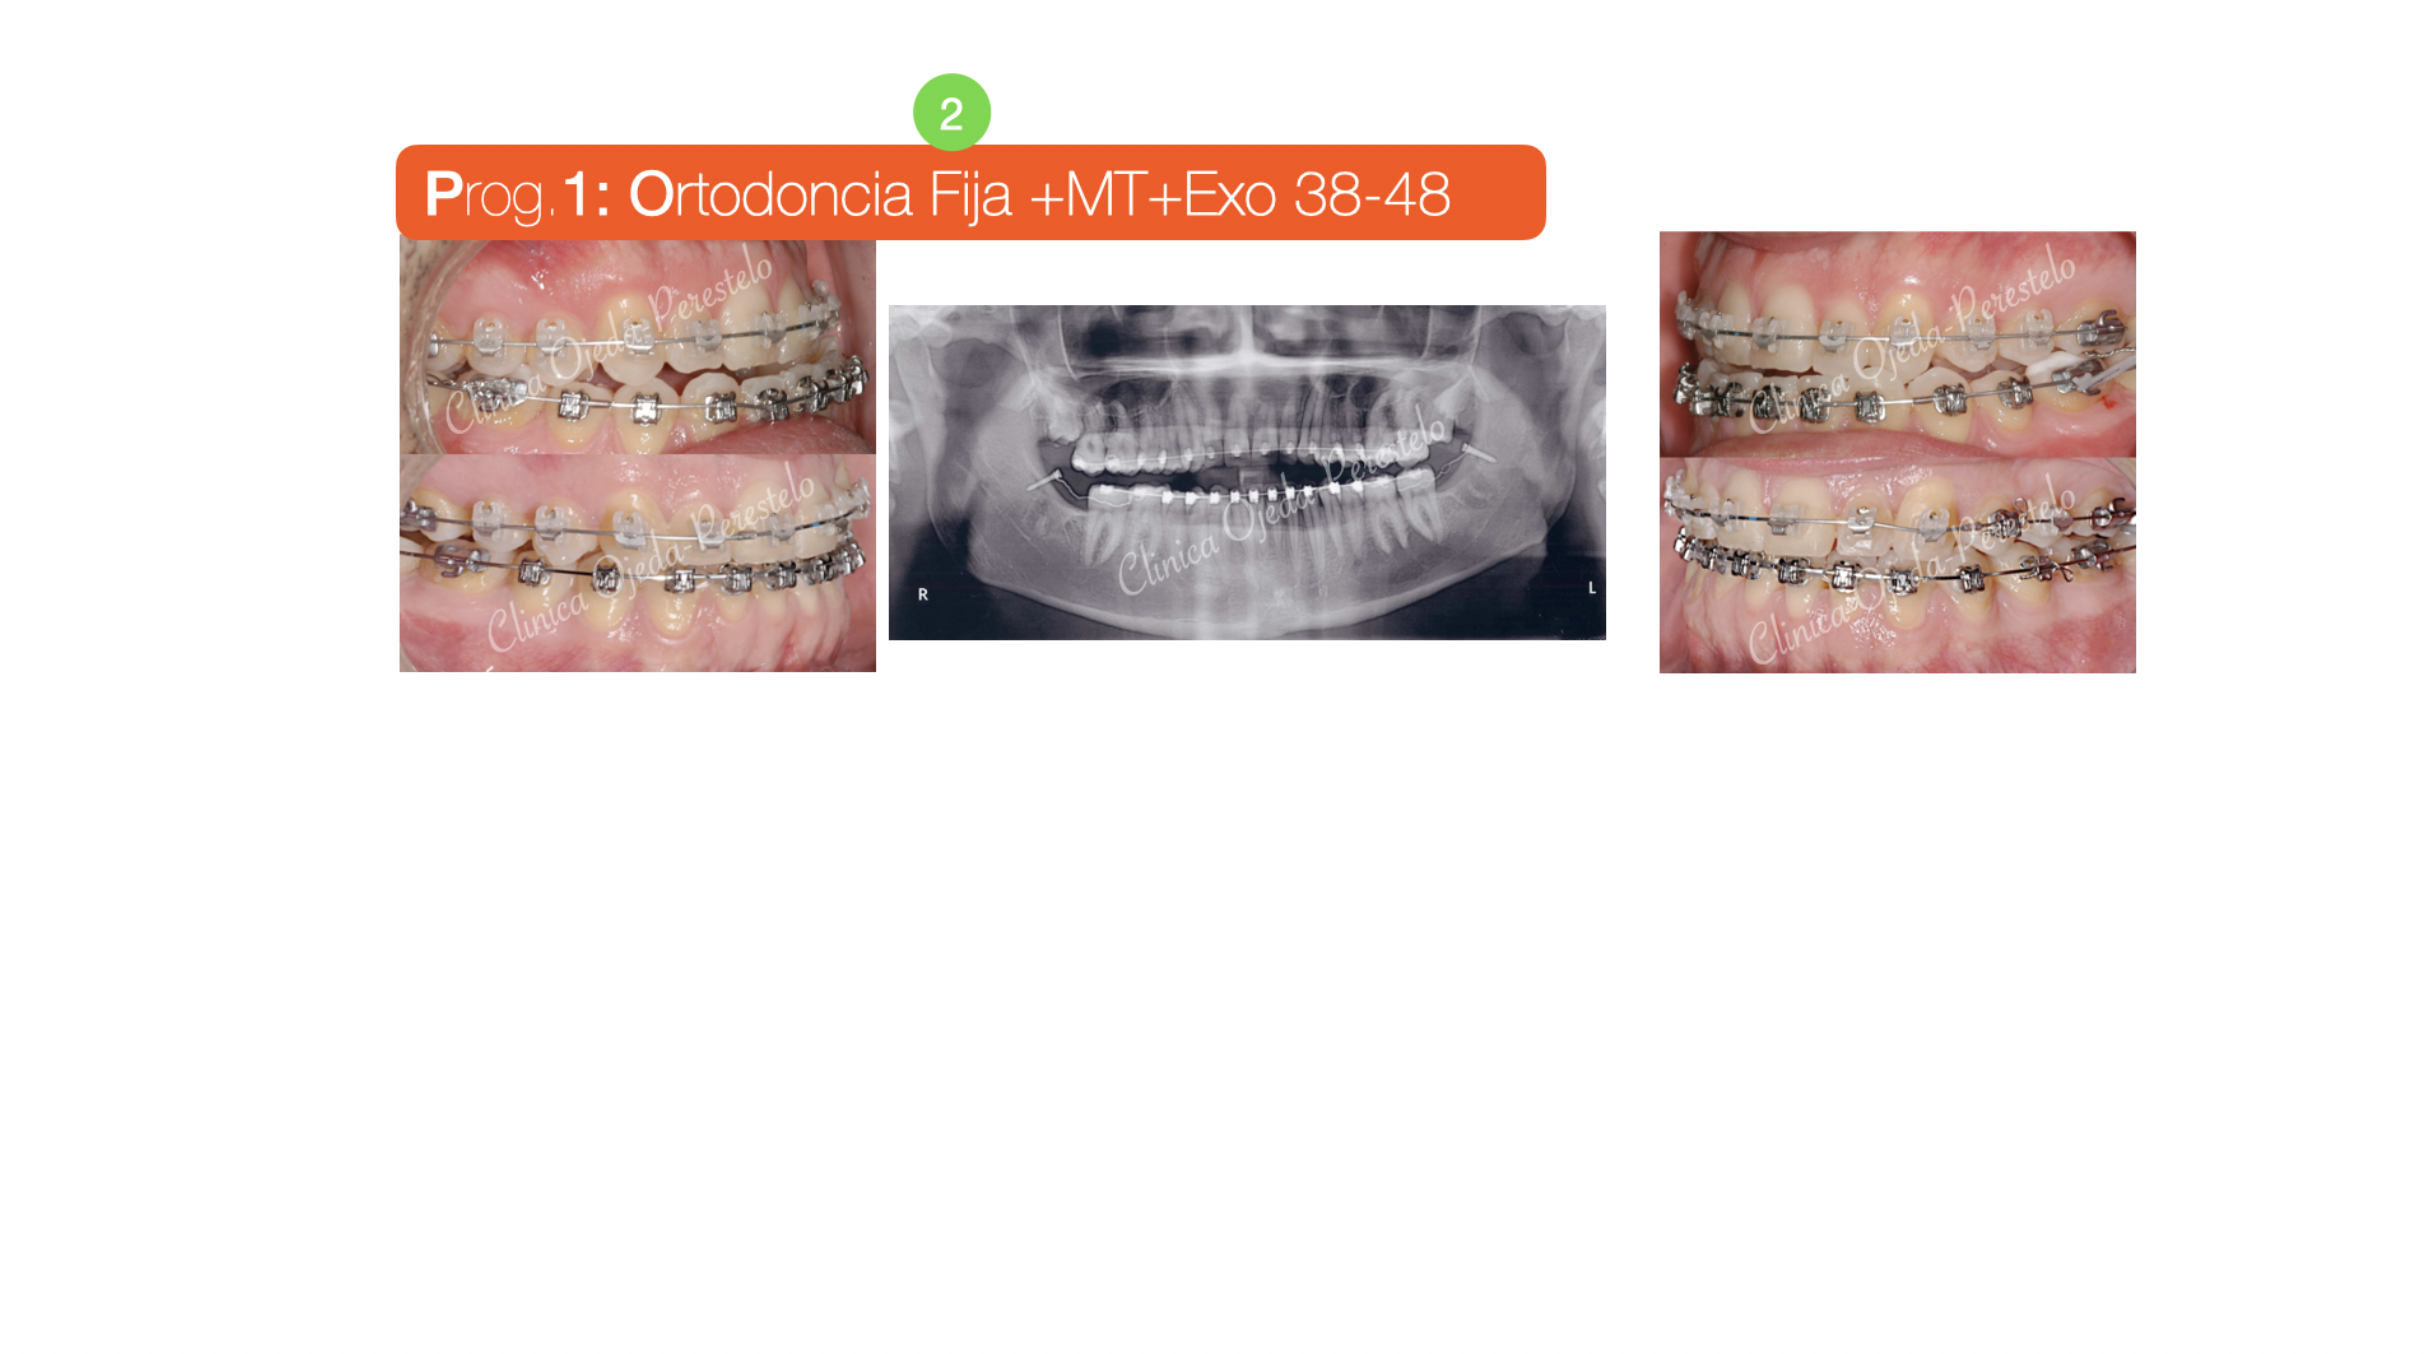

Clase III ósea tratada con Exo de cordales y Microtornillos

Paciente tratado con brackets de autoligado activo (Sistema In-Ovation) donde hemos alineado, nivelado y expandido ambas arcadas. Además hemos realizado las extracciones de los cordales inferiores y colocado Microtornillos para retruir la arcada mandibular al haber descartado el paciente la posibilidad de realizarse una cirugía ortognática.

Quisieramos destacar cómo hoy en día es posible distalizar y retruir con Microtornillos toda la arcada dentaria dotandole a estos casos de un adecuado resalte y sobremordida. Todo ello con una óptima cinemática mandibular.